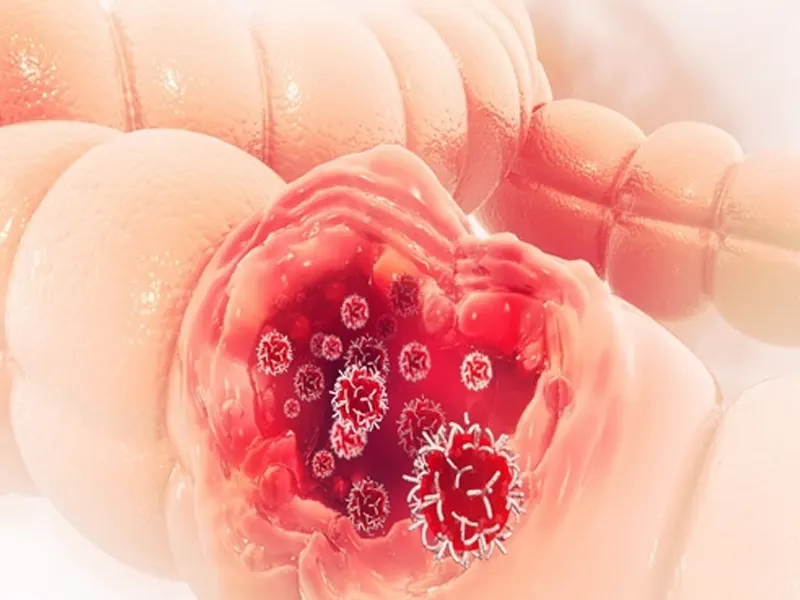

يشمل سرطان القولون والمستقيم سرطان القولون والمستقيم. يعد هذا السرطان أحد أكثر أنواع السرطان شيوعًا في العالم وفي إيران. وتعتبر زيادة معدلات السمنة، وتغيرات نمط الحياة، والعوامل الوراثية من بين الأسباب التي أدت إلى زيادة حالات الإصابة بهذا السرطان في السنوات الأخيرة.

أنواع سرطان القولون والمستقيم

سرطان الغدة الدرقية (النوع الأكثر شيوعًا)

أسباب سرطان القولون والمستقيم

تلعب العديد من عوامل الخطر دورًا في تطور هذا السرطان، وبعضها يشمل:

• النمو السرطاني (الزوائد اللحمية)

• الطفرات الجينية

أعراض سرطان القولون والمستقيم

يمكن أن تتنوع أعراض هذا السرطان، وفي المراحل المبكرة قد لا تكون هناك أي أعراض. مع تقدم المرض قد تظهر الأعراض التالية:

مراحل سرطان القولون والمستقيم

1. المرحلة الأولى: يقتصر السرطان على الطبقة المخاطية للقولون.

2. المرحلة الثانية: اخترق السرطان الطبقات العميقة من جدار الأمعاء.

3. المرحلة الثالثة: انتشر السرطان إلى الغدد الليمفاوية القريبة.

4. المرحلة الرابعة: انتشر السرطان إلى أعضاء أخرى في الجسم، مثل الكبد أو الرئتين.